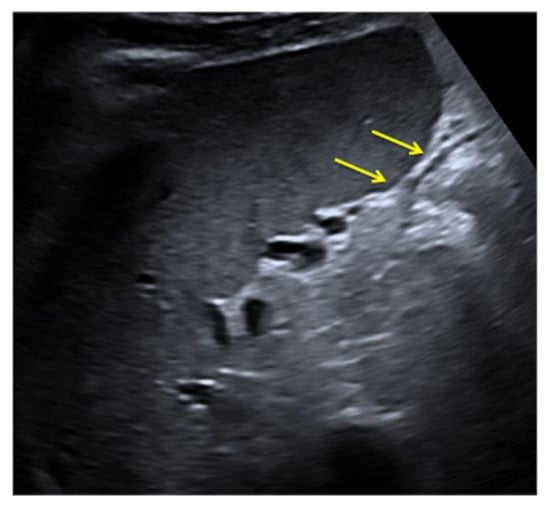

Figure 27. Coronal US scan of the left hypochondrium (a) is strongly influenced by the breakage of the probe crystals (arrows) and does not clearly show the large splenic hematoma. On CT scan (b) the splenic hematoma appears to be more evident (arrows).